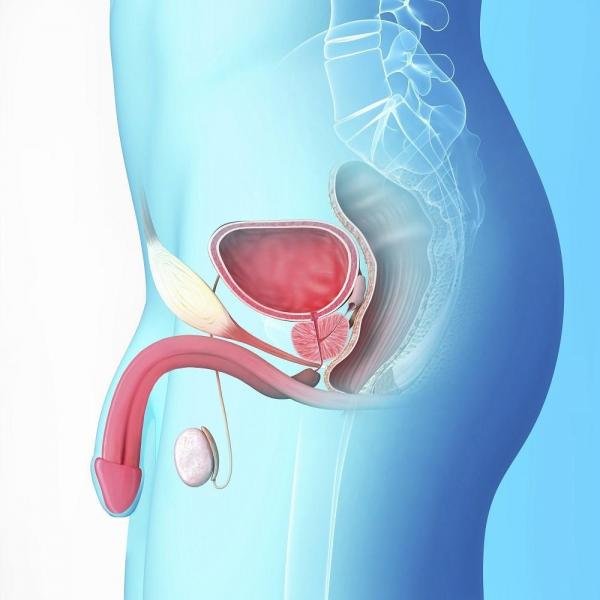

50 éves kor felett, bár ez a fánk alakú mirigy, ami körülveszi a húgycső, a has alsó (felelős termelő a prosztata folyadékot szállít, valamint védi a sperma) gyakran begyullad, vagy nagyítható. Ennek következtében összehúzódik az áramlás a vizelet a hólyagból.

A prosztata egy kis, de fontos mirigy (orgona) a férfi reproduktív rendszer. A fő szerepe a prosztata, hogy a folyadék, amely védi, táplálja a sperma. A prosztata mintegy egyharmada a folyadék, ami ejakulált (megjelent), a farka az orgazmus (orgazmus.).

Hol van a prosztata?

A fiatal férfi a prosztata körülbelül akkora, mint egy dió, de egyre nagyobb a korral. A prosztata ül a húgyhólyag alatt, körülveszi a felső része a húgycső. Vizelet halad keresztül a húgycső úton a hólyagból a pénisz.